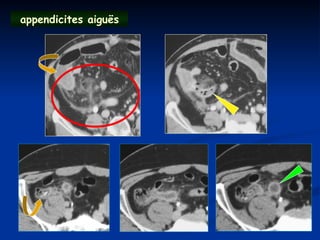

appendicites aiguës

Sémiologie Sémiologie  Augmentation du Augmentationdu diamètre transversal diamètre transversal  Epaississement pariétal Epaississement pariétal  Inflammation de la Inflammation de la graisse graisse périappendiculaire périappendiculaire  Stercolithe Stercolithe  Complications Complications ( phlegmon , abcès ) ( phlegmon , abcès )